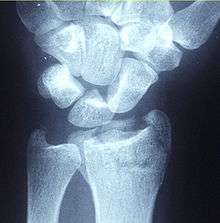

Diagnosis may be evident clinically when the distal radius is deformed but should be confirmed by X-ray. The differential diagnosis includes scaphoid fractures and wrist dislocations, which can also co-exist with a distal radius fracture. Occasionally, fractures may not be seen on X-rays immediately after the injury. Delayed X-rays, X-ray computed tomography (CT scan), or Magnetic resonance imaging (MRI) will confirm the diagnosis.

Medical imaging

X-ray of the affected wrist is required if a fracture is suspected. CT scan is often performed to investigate the articular anatomy of the fracture, especially if surgery is considered. Investigation of a potential distal radial fracture includes assessment of the angle of the joint surface on lateral X-ray, the loss of length of the radius from the collapse of the fracture, and congruency of the distal radioulnar joint. Displacement of the articular surface is the most important factor affecting prognosis and treatment.